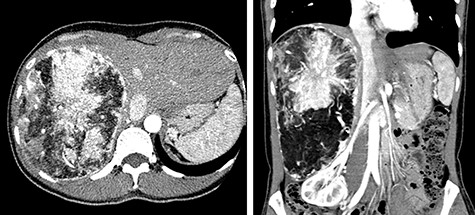

A 45-year-old woman was referred to our hospital with a huge liver tumor, which had been diagnosed as HAML 5 years previously when it was 12 cm in diameter (Fig. 1). Periodic follow-up with ultrasound and magnetic resonance imaging after the initial diagnosis had shown a progressive increase in the size of the tumor, and by the time of referral it measured 20 × 14 cm and had become symptomatic. On admission, enhanced computed tomography revealed a very large, well-defined, mixed-density mass occupying the entire right lobe of the liver (Fig. 2). Angiography showed dilated and tortuous vessel inside the tumor, and a drainage vein from the tumor to the right hepatic vein was visualized in the early phase (Fig. 3).

Abdominal computed tomography (CT) 5 years before referral to our hospital; enhanced CT revealed mixed density tumor measuring 12 × 10 cm in the right lobe of the liver; a peritumoral early drainage vein around the tumor (arrow heads) was visualized.